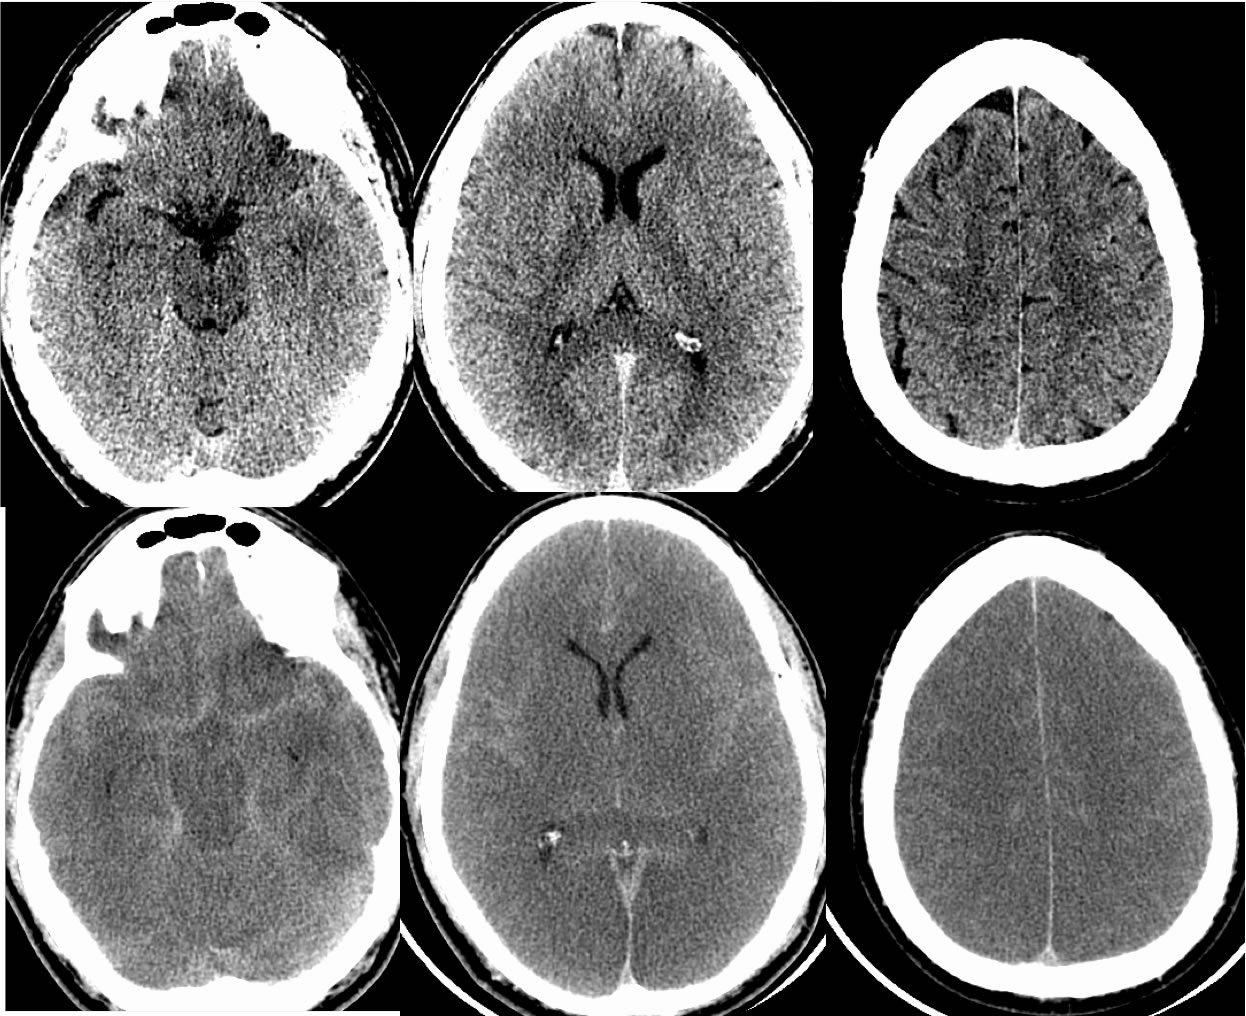

CT brain scan after deterioration showing massive brain swelling, note Can Medicine Cause Brain Swelling Brain swelling is typically due to an injury or an underlying. Brain swelling is a buildup of fluid in and around your brain. Cerebral edema, also known as brain swelling, is a critical condition characterized by an increase in brain volume due to excessive fluid accumulation. Doctors will use drugs to reduce swelling or blood clots. Examples include warfarin, which. Can Medicine Cause Brain Swelling.